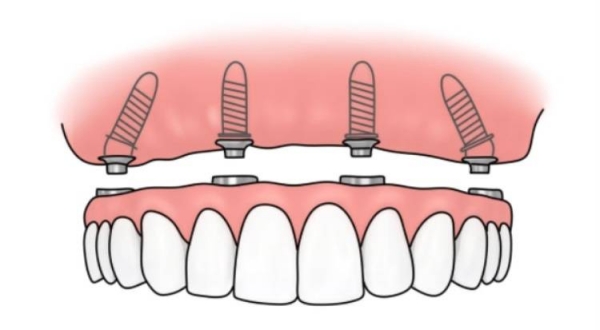

值得注意的是,60歲以上老年患者憑有效身份證件可享受種植牙項(xiàng)目9折優(yōu)惠,同時(shí)醫(yī)院還提供分多次付款服務(wù),減輕患者經(jīng)濟(jì)壓力。對(duì)于全口或半口牙缺失患者,醫(yī)院推出All - on - 4等綜合治療方案,價(jià)格16990元起,相比單顆種植可節(jié)省約30%費(fèi)用。